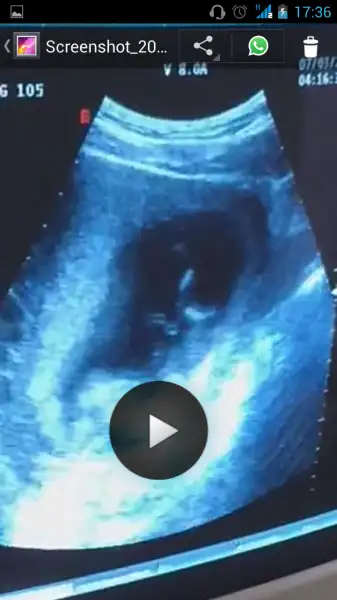

Benimkine de bakarmisiniz rica etsem 11 haftalık

• 1000926651.webp

1000926651.webp

18,2 KB · Görüntüleme: 16